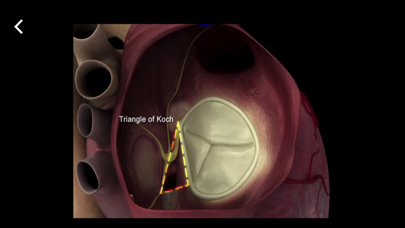

Mitral & Tricuspid Valves

от Edwards Lifesciences

TEE Evaluation of the Mitral and Tricuspid Valves